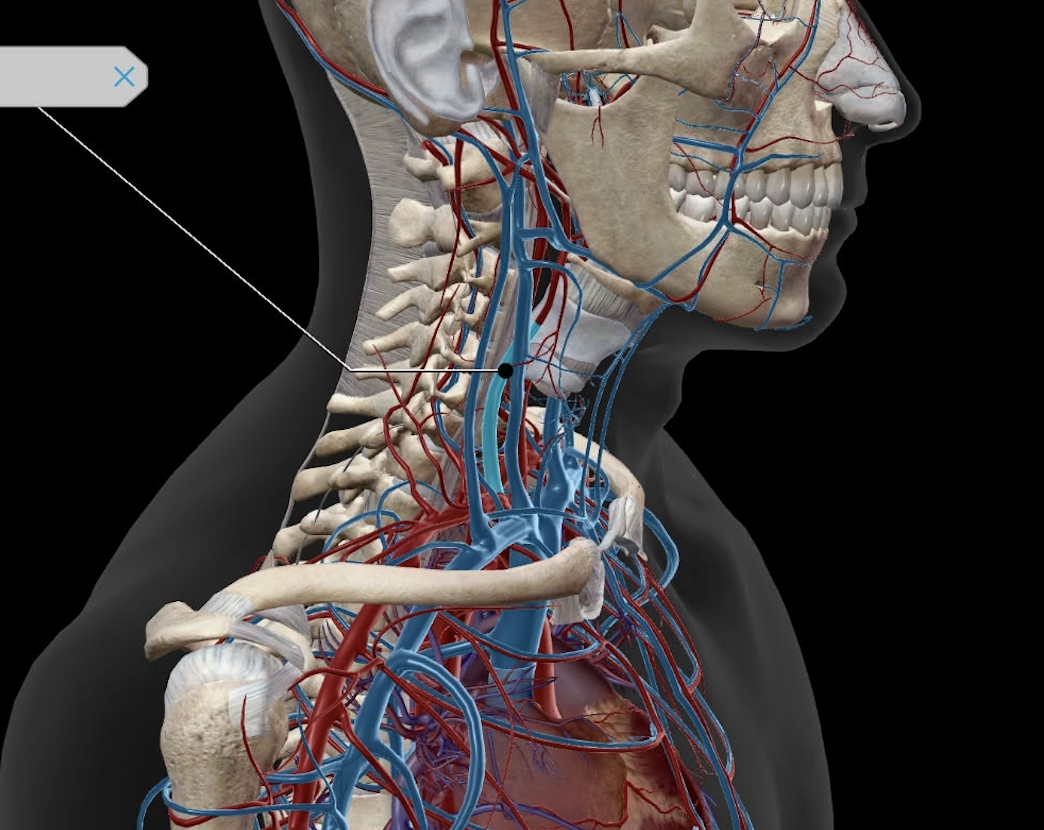

Common Carotid Artery

Internal Jugular Vein

External Jugular Vein